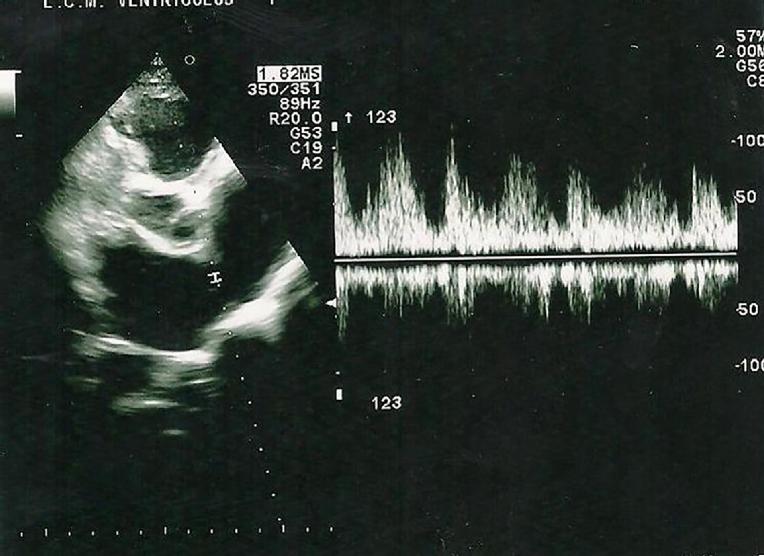

From www.researchgate.net

Echocardiographic assessment of an athlete with right ventricle Athlete Irregular Heartbeat anatomically, the disease is characterized by generalized or localized hypertrophy of the left ventricle. why cyclists, runners, and other athletes in otherwise impeccable health are sometimes at risk is poorly understood, and could involve both. although many assume that those that do cardiovascular exercise regularly are less likely to develop heart issues, recent research found that. . Athlete Irregular Heartbeat.